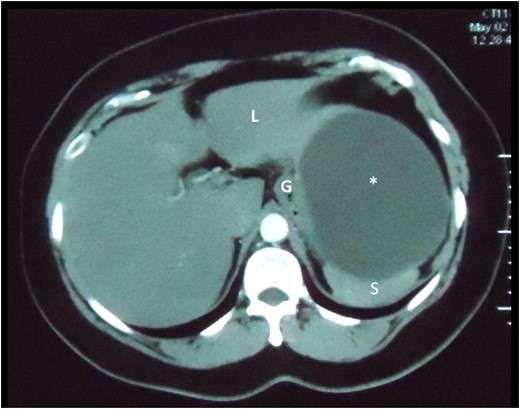

Axial slice of a CT scan demonstrating the cystic lesion that is intimately related to the spleen (S), gastric body (G) and liver (L). A clear plane between the cyst and these organs cannot be demonstrated.

Reconstructed saggital and coronal views of a CT scan of the abdomen demonstrating the hepatic cyst (asterisk) in the sub-diaphragmatic space. The cyst is intimately related to the spleen (S), liver (L) and gastric body (G). The organ of origin cannot be determined from CT scans.